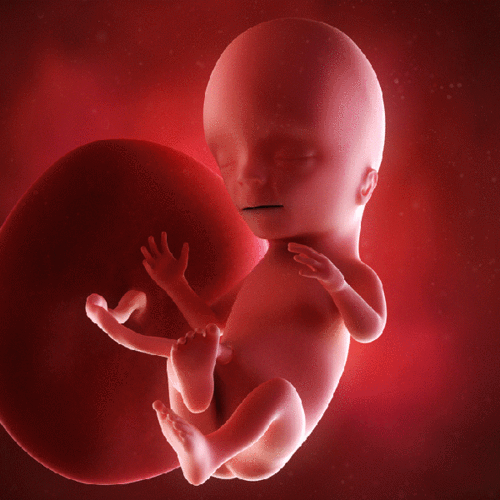

进入4个月,胎儿的小耳朵从这个月起可以听到子宫外的声音了.

进入4个月,我的小耳朵从这个月起可以听到子宫外的声音了,呵呵.

【宝宝胎动】胎动:看看宝宝们在肚子里怎样大闹天宫的